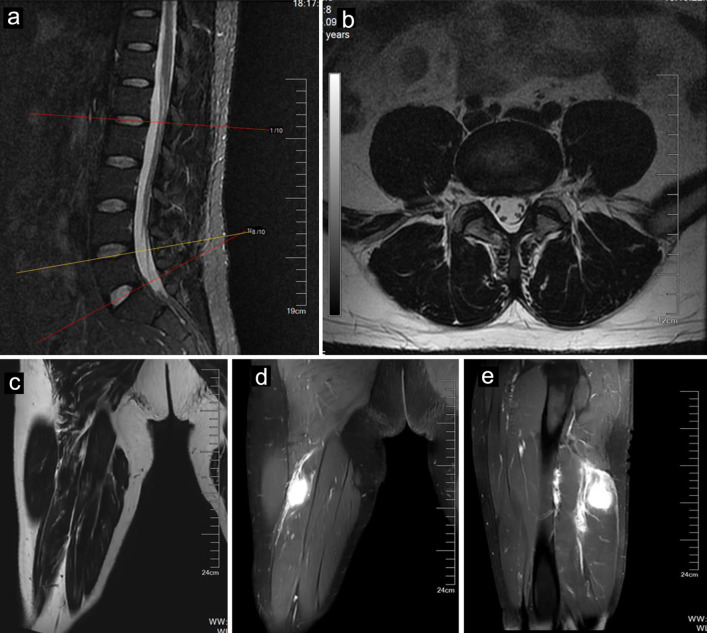

炎性肌纤维母细胞瘤(IMTs)是一种纤维母细胞和肌纤维母细胞混合增殖并伴有炎性浸润的肿瘤,在四肢中极为罕见。目前还没有涉及坐骨神经的坐骨神经瘤的报道。这种类型的受累可能会导致坐骨神经卡压,其症状可能与腰椎间盘突出症(LDH)相似,尤其是发生在腰椎间盘退行性疾病患者身上时。我们描述了一例 40 岁男性患者的病例,他患有腰椎间盘退行性病变并伴有坐骨神经 IMT,其症状与 LDH 相似,给诊断带来了挑战。我们展示了该病的病程以及累及坐骨神经的IMT的系统影像学表现,并讨论了其治疗方法。

Inflammatory myofibroblastic tumors (IMTs), which involve the proliferation of fibroblastic-myofibroblastic cells mixed with inflammatory infiltrates, are exceedingly rare in the extremities. There are no reported IMTs involving the sciatic nerve. This type of involvement may cause entrapment of the sciatic nerve, whose symptoms may mimic lumbar disc herniation (LDH), especially when it occurs in patients with lumbar degenerative disc disease. We describe the case of a 40-year-old male with lumbar degenerative disc disease accompanied by IMT involving the sciatic nerve whose symptoms mimicked LDH and posed a diagnostic challenge. We showed the course of the disease as well as the systematic imaging manifestations of IMTs involving the sciatic nerve and discussed their therapeutic management.